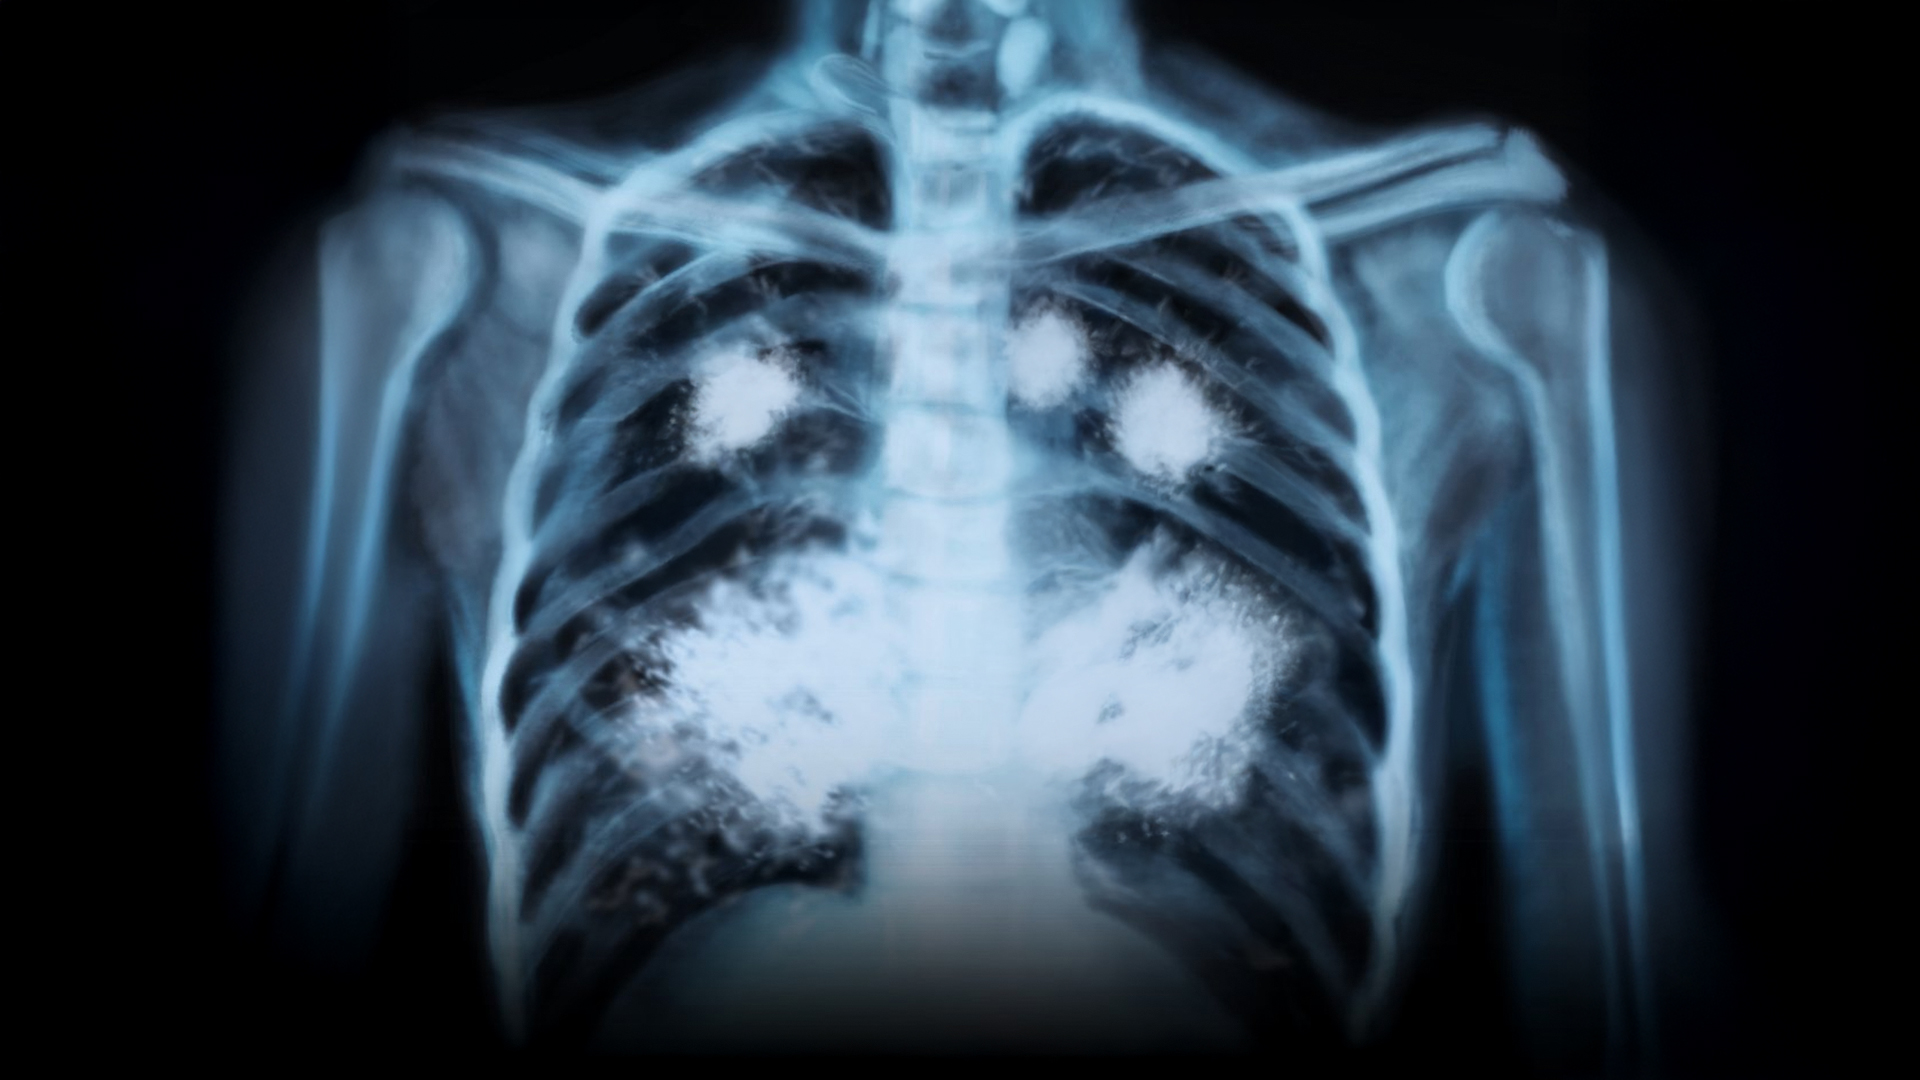

👉 El vapeo puede causar una enfermedad pulmonar rara, irreversible y mortal.

Se llama bronquiolitis obliterante, y destruye poco a poco los bronquiolos de los pulmones.

Provoca tos, falta de aire, dolor al respirar y, con el tiempo, deja los pulmones completamente dañados.